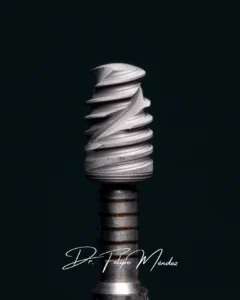

- Marcas de Prestigio: Utilizamos marcas reconocidas mundialmente y usadas en Chile como Hiossen / Osstem, BioHorizons, S.I.N., MIS y Straumann, entre otros.

- Tipo de Implante: dentro de la misma marca existen lineas de implantes con diversas características ej. tratamientos de superficie, ultra cortos, slim (delgados), etc.

Calidad de la Corona: Trabajamos con coronas digitales de material CAD/CAM fresado (Zirconio u otro), lo que garantiza un ajuste perfecto y una estética natural superior a la metal-cerámica antigua.